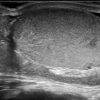

Viêm tinh hoàn - mào tinh

Viêm tinh hoàn – mào tinh

» Thông tin: Nam giới – 34 tuổi.

» Lâm sàng: Sưng đau vùng bìu.

# Tăng kích thước và tín hiệu mạch trên doppler tinh hoàn và mào tinh hoàn.